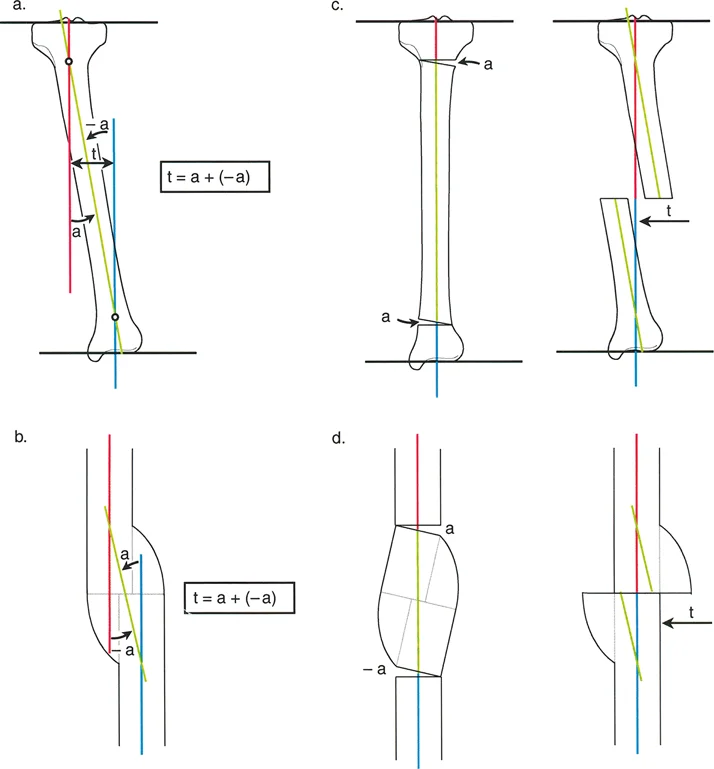

2. التدخل الجراحي: قطع العظم (Osteotomy)

العملية الجراحية الأكثر شيوعاً لتصحيح تشوه الانزياح هي "قطع العظم" (Osteotomy). تتضمن هذه العملية قطع العظم في مستوى التشوه أو بالقرب منه، ثم إعادة محاذاة أطراف العظم وتثبيتها في الوضع الصحيح.

- مبادئ تصحيح الانزياح:

- قطع عظم واحد مع تصحيح الانزياح المباشر: يتم قطع العظم في مستوى الانزياح، ثم يتم تحريك أطراف العظم مباشرة لإعادة المحاذاة وتثبيتها.

- قطع عظمين مع تصحيح زاوي معاكس: يمكن تصحيح الانزياح عن طريق إجراء عمليتي قطع عظم في مستويين مختلفين، مع تصحيح زاوي معاكس في كل مستوى. هذا النهج يسمح بإعادة المحاذاة دون إزاحة مباشرة لأطراف العظم في مستوى القطع.

خطوات العملية الجراحية (بشكل عام):

- التخطيط الدقيق: قبل الجراحة، يقوم الأستاذ الدكتور محمد هطيف بإجراء تخطيط جراحي مفصل باستخدام صور الأشعة السينية والتصوير المقطعي المحوسب. يتضمن ذلك تحديد الموقع الدقيق للقطع، مقدار التصحيح المطلوب، ونوع التثبيت الذي سيتم استخدامه.

- الوصول الجراحي: يتم عمل شق جراحي للوصول إلى العظم المتأثر.

- قطع العظم: يتم قطع العظم بدقة باستخدام أدوات جراحية متخصصة.

- إعادة المحاذاة: يتم تحريك أطراف العظم بعناية لإعادة محاذاتها في الوضع الصحيح، مع تصحيح الانزياح وأي انحرافات زاويّة مصاحبة.

- التثبيت: بعد إعادة المحاذاة، يتم تثبيت العظم باستخدام: